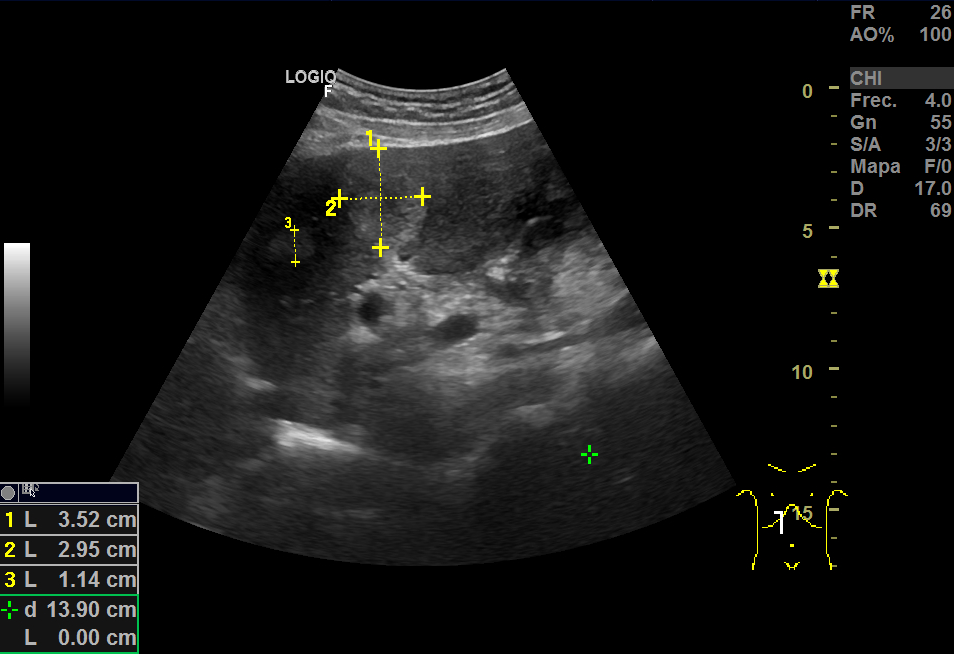

En la ecografía, a nivel hepático, vimos unas imágenes hiperecoicas redondeadas hipervascularizadas: una de aproximadamente 5 cm de diámetro y otra de 3cm, sospechosas de LOEs (lesiones ocupantes de espacio).

Repite la ecografia: En el segmento IV, aparece una imagen redondeada de 30x40 mm heterogénea, iso-hipoecogénica sin captación ecodoppler que podría ser un angioma, HFN (hiperplasia nodular focal) u otra posibilidad; otra imagen oval hiperecogénica de 19 mm, que sugiere angioma como primera posibilidad.

El aspecto de los hemangiomas hepáticos en la ecografía son lesiones de pequeño tamaño (inferior a 30 mm), hiperecoicas, bien delimitadas, homogéneas, con refuerzo acústico posterior y sin captación en el estudio Doppler. En cambio, el aspecto ecográfico atípico como el de nuestro caso: mayor tamaño, heteroecoico con zona central hipoecoica y límites irregulares o mal definidos, requiere de otras técnicas.